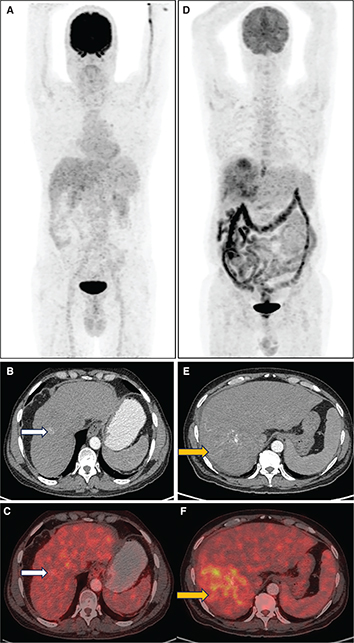

Detection of primary HCC using 18F-FDG PET/CT alone is limited, with a relatively low sensitivity (approx. 50–65%) compared to current standard of care imaging. Higher grades of HCC (less differentiated) tend to have higher FDG avidity, whereas well-differentiated HCC shows relatively low 18F-FDG uptake (3). This results from the varied expression of glucose transporters (GLUT) and increased glucose-6-phosphatase activity in well differentiated HCC while poorly differentiated HCC has loss of glucose-6-phosphatase activity. In a study by Torizuka et al., the degree of differentiation of HCC was correlated with 18F-FDG uptake, with higher-grade tumors showing twice FDG uptake compared to lower-grade tumors (4). Dual point imaging can be performed, in addition to the conventional imaging 1-hour after FDG injection, to increase the sensitivity of 18F-FDG PET/CT to detect HCC (5). Figure 1 shows 18F-FDG PET/CT findings in primary HCC.

Fig 1

Figure 1. 18F-FDG PET/CT in HCC. A. Maximum Intensity Projection (MIP) image of 18F-FDG PET/CT in a patient with well-differentiated HCC shows no abnormal increased tracer uptake in the liver. Corresponding CT (B) and fused PET/CT (C) images for the same patient show non-FDG avid arterially enhancing lesion in segment VIII of liver, consistent with primary HCC (white arrows). D. Maximum Intensity Projection (MIP) image of 18F-FDG PET/CT in a patient with poorly differentiated HCC showing areas of increased FDG uptake in the liver. Corresponding CT (E) and fused PET/CT (F) images in the second patient show FDG avid (SUVmax 9.4) arterially enhancing mass involving the segments VI and VII of liver (yellow arrows).